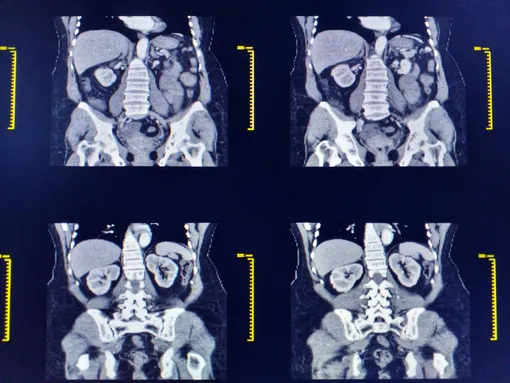

Как проходит КТ

А вот при КТ никакого тоннеля не будет. Вам предстоит прийти в мягкой простой хлопковой одежде, снять все металлические украшения и так же лечь на выдвижной диагностический стол. Вокруг вас будет двигаться «бублик» и сканировать вас рентгеном с разных сторон. Иногда врачи будут просить задержать дыхание. Длится процедура около от 5 до 30 минут, в зависимости от зоны исследования. Как и при МРТ, ни спать, ни двигаться не надо.

На самом деле открытие КТ было прорывом в медицине, за который создатели Годфри Хаунсфилд и Аллан Кормак получили Нобелевскую премию в 1979 году. Если вы когда-нибудь проходили КТ, вы наверняка замечали, как вокруг вас что-то методично крутилось. Благодаря такому снимку на 360 градусов можно построить 3D-модель вашего «внутреннего мира»!

Но причем тут компьютер? Дело в том, что одних рентгеновских снимков с разных ракурсов недостаточно. Необходимо программное обеспечение, которое может считать все сигналы с детекторов и соединить получившиеся снимки в единое изображение.

Рентгенограф видит, где кости, где мягкие ткани, а где газы (обычно они подсвечиваются для врачей черным цветом). Кстати, при КТ с контрастом желудочно-кишечного тракта в качестве контраста используют сульфат бария: он обволакивает слизистые, тем самым подчеркивая рельеф, например, кишечника. Выводится тоже быстро: максимум через 48 часов. Обычно КТ с контрастом используется для выявления и изучения патологий жизненно важных органов: мозга, сердца, печени, желудка, кишечника и др.

- Качество изображения. У КТ разрешение побольше, что делает ее «золотым стандартом» для визуализации костей, легких и острых кровоизлияний. МРТ, в свою очередь, обеспечивает превосходный контраст мягких тканей, поэтому незаменима для исследования головного и спинного мозга, связок, суставов и опухолей.